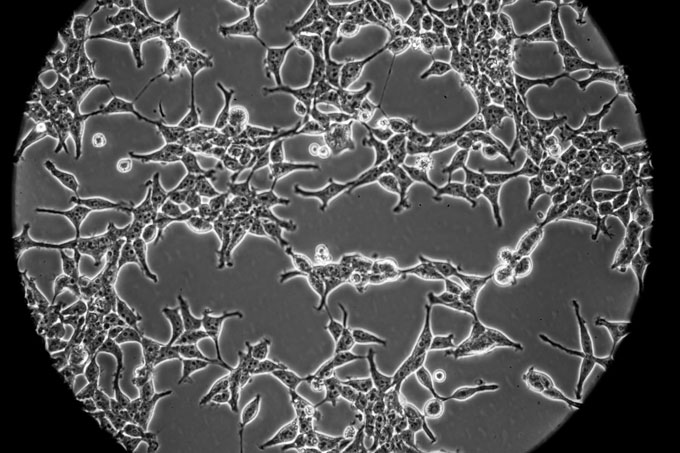

Cell lines are cultures of human or other animal cells that can be grown for long periods of time in the lab. Some of these cultures are known as immortalized cell lines because the cells never stop dividing. Most cells can’t perform this trick — they eventually stop splitting and die. Immortal cell lines have cheated death. Some are more than 50 years old.

Cell lines can be manipulated to become immortal. Or sometimes, immortality arises by chance. “Whenever people make primary cell cultures from different organs of different animals, every so often you just get … lucky, and some cultures just won’t die,” explains Matthew Koci, a viral immunologist at North Carolina State University in Raleigh. Such long-lasting cell lines go on to get studied, and studied some more. Some end up being used in labs around the world.

Immortalized cell lines are crucial for many different types of biomedical research, not just vaccines. They’ve been used to study diabetes, hypertension, Alzheimer’s and much more. Some are human cells, but many also come from animal models. For example, many COVID-19 studies — beyond just those related to vaccines — are using Vero cells, a cell line derived from the kidney of an African green monkey, Rasmussen says.

HEK-293 cells, for example, are especially useful for vaccine work, Rasmussen explains. It’s easy to put new viral genes in them, she says, and once they have the genes inside, HEK-293 cells can pump out large amounts of viral protein — exactly what’s needed to help people develop an immune response.

HeLa are also relatively easy to work with. They can be used to analyze how the coronavirus enters cells to hijack their machinery, for example. “It’s great to have them in the arsenal,” Rasmussen says. But, she says, it’s important to “think about their origins.”